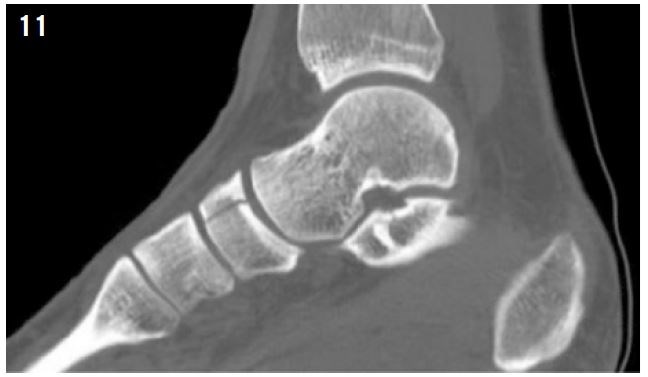

Diagnosis is made by MRI or CT scan (Figure 11).

Screw fixation is recommended in athletes (Figure 12). Return to sports activity can be expected at 4 months post-op35.

Figure 11: Navicular bone fracture visualized by CT Scan.

Figure 12: Navicular bone fracture fixed by double screwing.